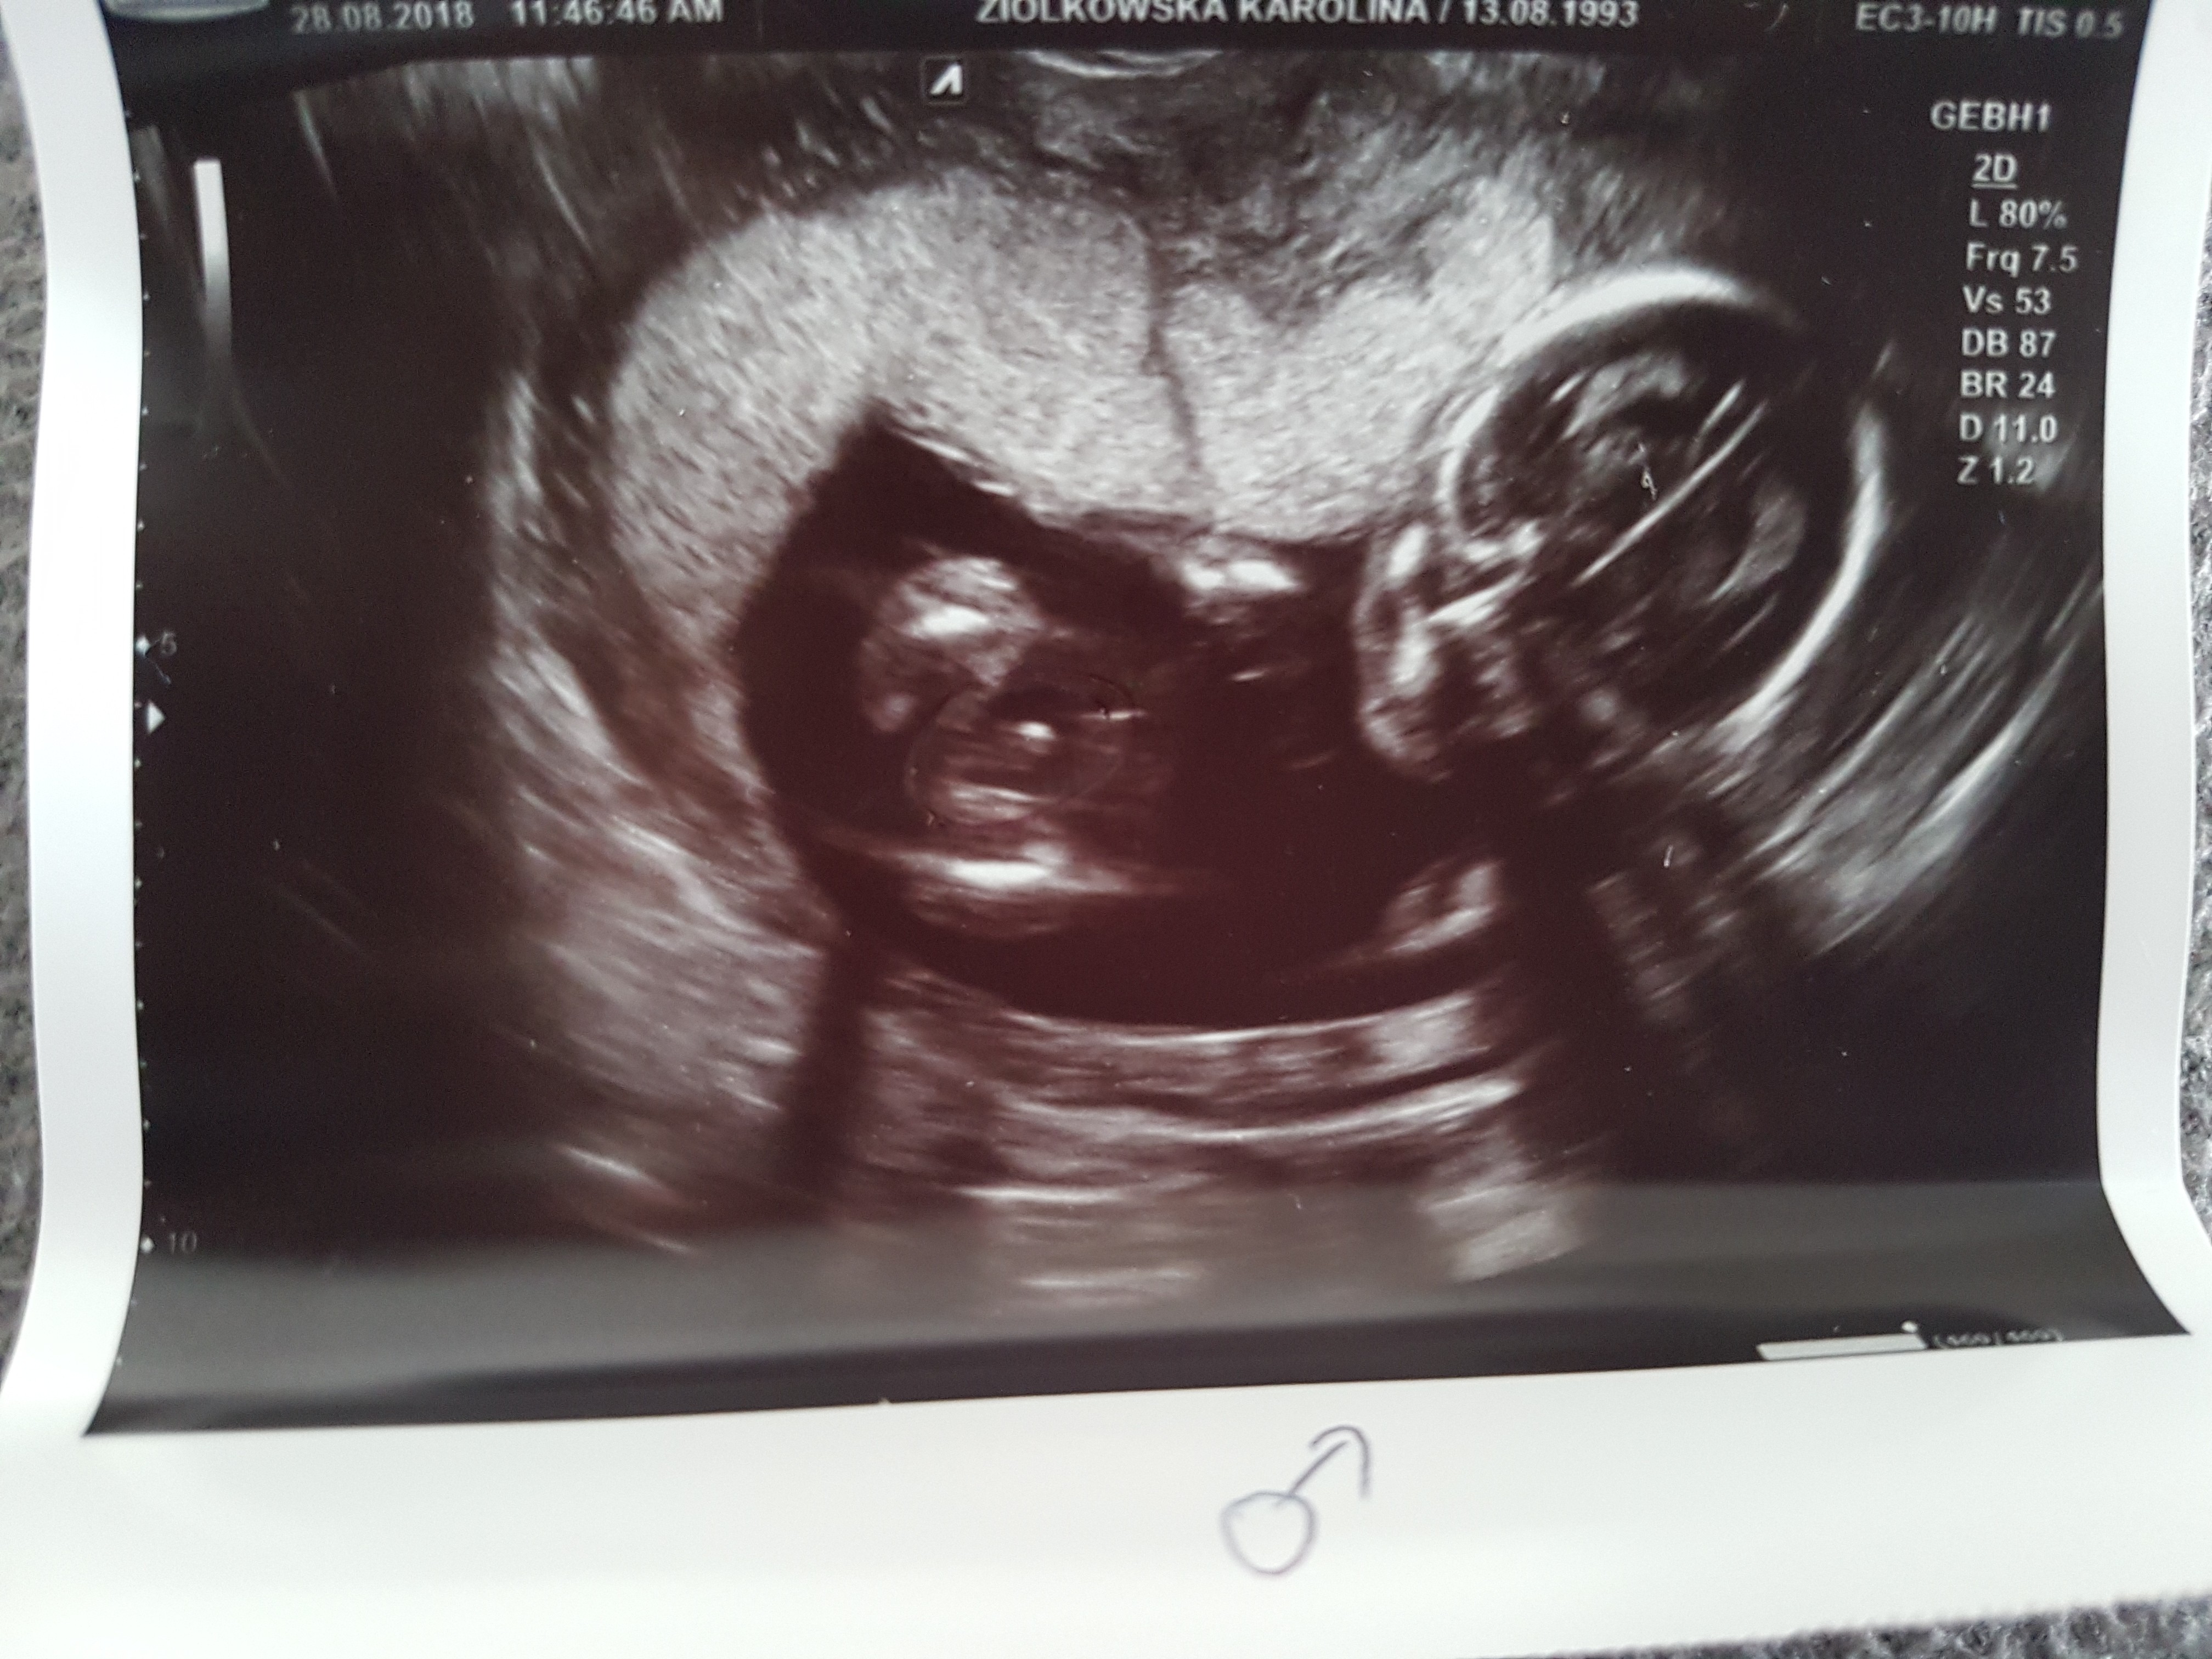

Dziewczyny, bylam dzis na wizycie 17 tc, Pani doktor powiedziała, że chłopak na 90 %. Co myślicie?

20180828_145447.jpg

• 20180828_145447.jpg

1,8 MB · Wyświetleń: 2 316